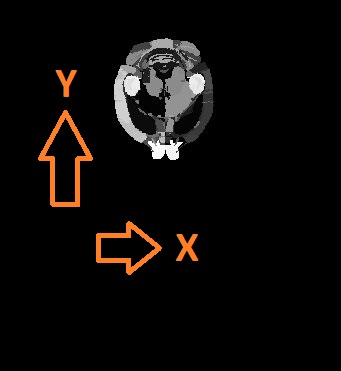

Sample orientation

As you can see in the previous figure and the figure on the top, the histological images and the target volume do not necessarily have the same orientation. This can be corrected in the S2V GUI. Also, the

- Initial input rotation: If, as shown above, the histological image has a different orientation than the atlas, you can either rotate the atlas or specify a degree (ideally multiple of 90) to rotate the histological image before registration

- Symmetry correction: This is relevant if, for instance your atlas was previously warped to match another data source (MRI, CT, etc). In that case, the atlas may be tilted (see figure below). The registration goes through the volume stack from slice to slice, it is assumed that the orientations match. If the atlas is tilted as shown below, this will not work any more. The symmetry correction provides a way out by rotating the atlas round the specified axis, until it is horizontally symmetrical.

|

|

|---|---|

| Axial overlay of atlas and a CT: This atlas requires a symmetry correction. | Symmetry correction directions with respect to the plane orientation in the volumetric input |